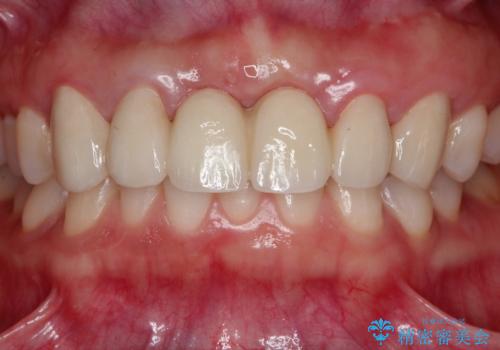

前歯 ブリッジ周囲の腫れた歯ぐきを改善

- 数ヶ月前に治療終了したブリッジの歯ぐきの違和感が強く、改善を求めて来院されました。

歯ぐきは著しく腫れ、少し触ると出血してしまうような状態であったためブリッジの再作製・歯周外科を用いた歯肉環境の改善を計画します。